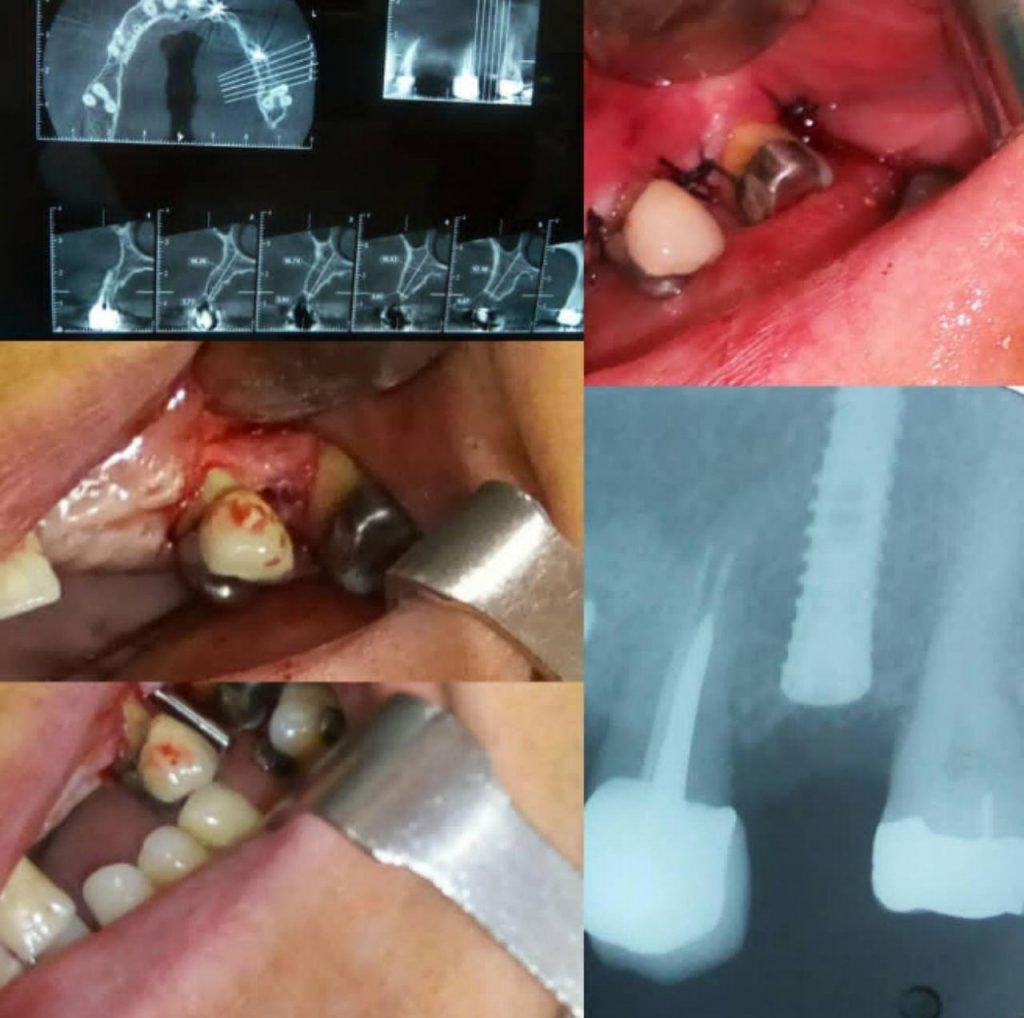

• عکسبرداری و رادیوگرافی از دندان

برای تشخیص میزان و سطح آسیب و همچنین تعیین روش مناسب جهت درمان ریشه دندان، متخصص درخواست عکسبرداری و رادیوگرافی دندان را می دهد.

• انجام بی حسی و برداشتن تاج دندان

بعد از اینکه معاینات اولیه انجام شد، با انجام بی حسی موضوعی در فک شما، دندانپزشک اقدام به برداشتن قسمت کمی از تاج دندان می کند و سطح پوسیده به طور کامل برداشته می شود.

• تخلیه پالپ عفونی شده

زمانی که ریشه دندان ظاهر شد، امکان دسترسی دندانپزشک به پالپ عفونی شده وجود دارد و به طور کامل کانال ریشه دندان را از آن تخلیه می کند. توجه به این نکته ضروری است که عروق عصبی پالپ به طور کامل قطع شوند، تا در آینده باعث مشکل و درد برای فرد نشوند.